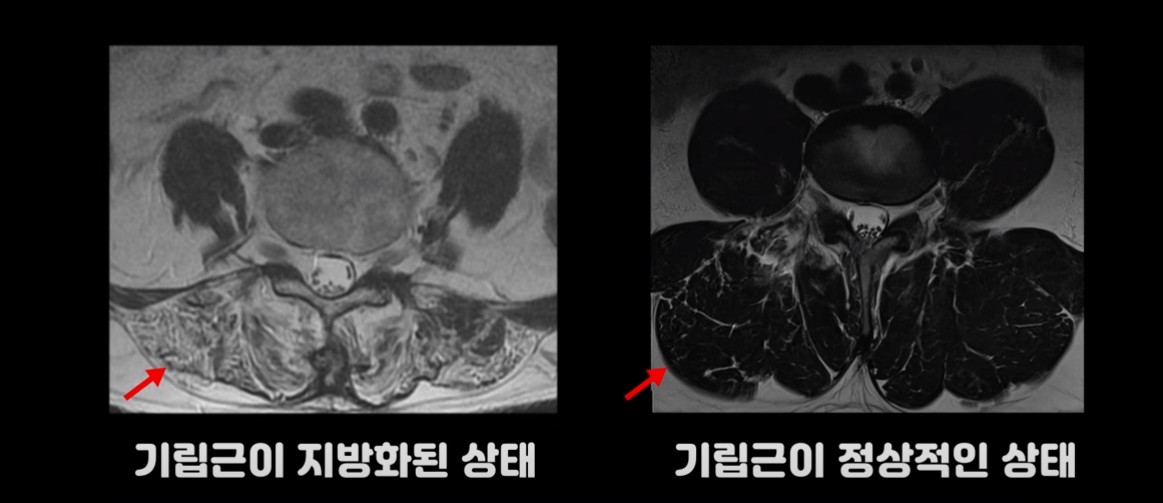

여기 허리가 많이 구부러지는 70세 이후 환자분의 MRI를 보시겠습니다.

이 환자분의 기립근을 보면 MRI상 어둡게 보여야 할 근육이 사진에서 보는 것 같이 하얗게 보입니다. 근육이 지방으로 변해 버린 겁니다. 또 근육의 크기도 위축되어 많이 작아져 있습니다.

기립근이 정상적인 상태의 MRI 사진과 비교해 보면 확연하게 차이를 느끼실 겁니다.